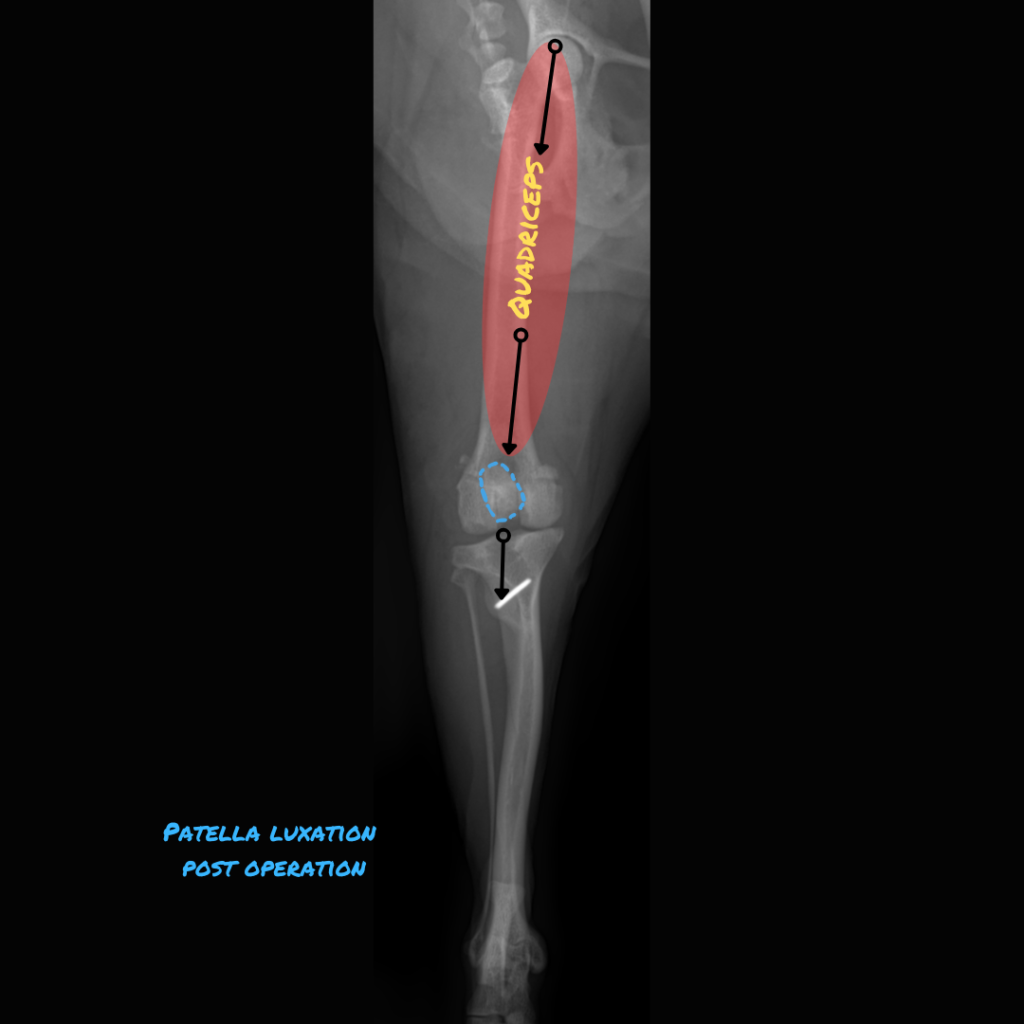

Patellar luxation occurs when the kneecap slips out of its groove, shifting medially or laterally. The patella is embedded within the tendon that connects the quadriceps muscle to the tibial tuberosity, assisting in knee straightening. The patella shields the tendon as it glides over the end of the thigh bone.

[Pic 2: The tibial tuberosity was shifted laterally and the groove was made deeper, so the patella is now sitting in its proper spot in the middle. (blue dotted line)